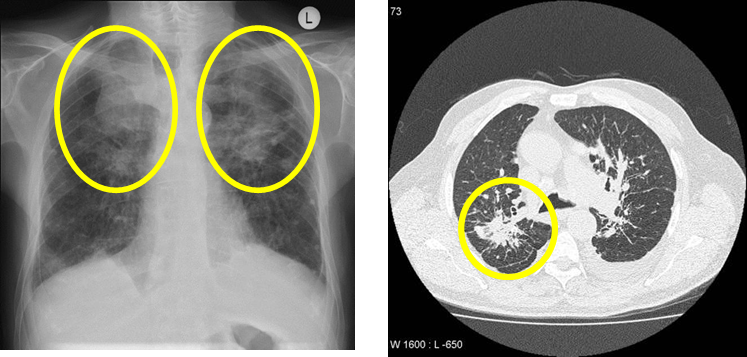

• acute silicosis: difuse miliary infiltration, “crazy paving” (diffuse GGO + septal thickening)

• chronic silicosis

• variably sized nodules, predominating in upper lobe

• calcification of hilar nodes (eggshell calcification)

• irregular masses >1cm → mass가 합쳐지면서 progressive massive fibrosis (PMF) 발생